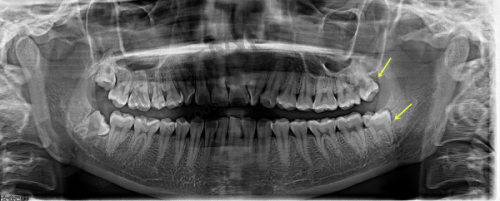

贵阳牙博士吴可伦种植牙实例

曾经有一位全口牙齿缺失的患者,长期以来饱受咀嚼不便和面容塌陷的困扰。吴可伦医生为他制定了全口种植的方案,采用精良的数字化种植技术和即刻负重技术。手术过程非常顺利,患者在短时间内就拥有了新的牙齿,不仅咀嚼功能得到了极大的改善,面容也修复了饱满,整个人的精神状态都焕然一新。

还有一位上颌后牙区牙槽骨高度不足的患者,吴可伦医生为其进行了上颌窦内外提升手术,增加了骨高度后成功进行了种植牙手术。术后患者的种植牙稳固,使用成效良好,对治疗成效非常满意。